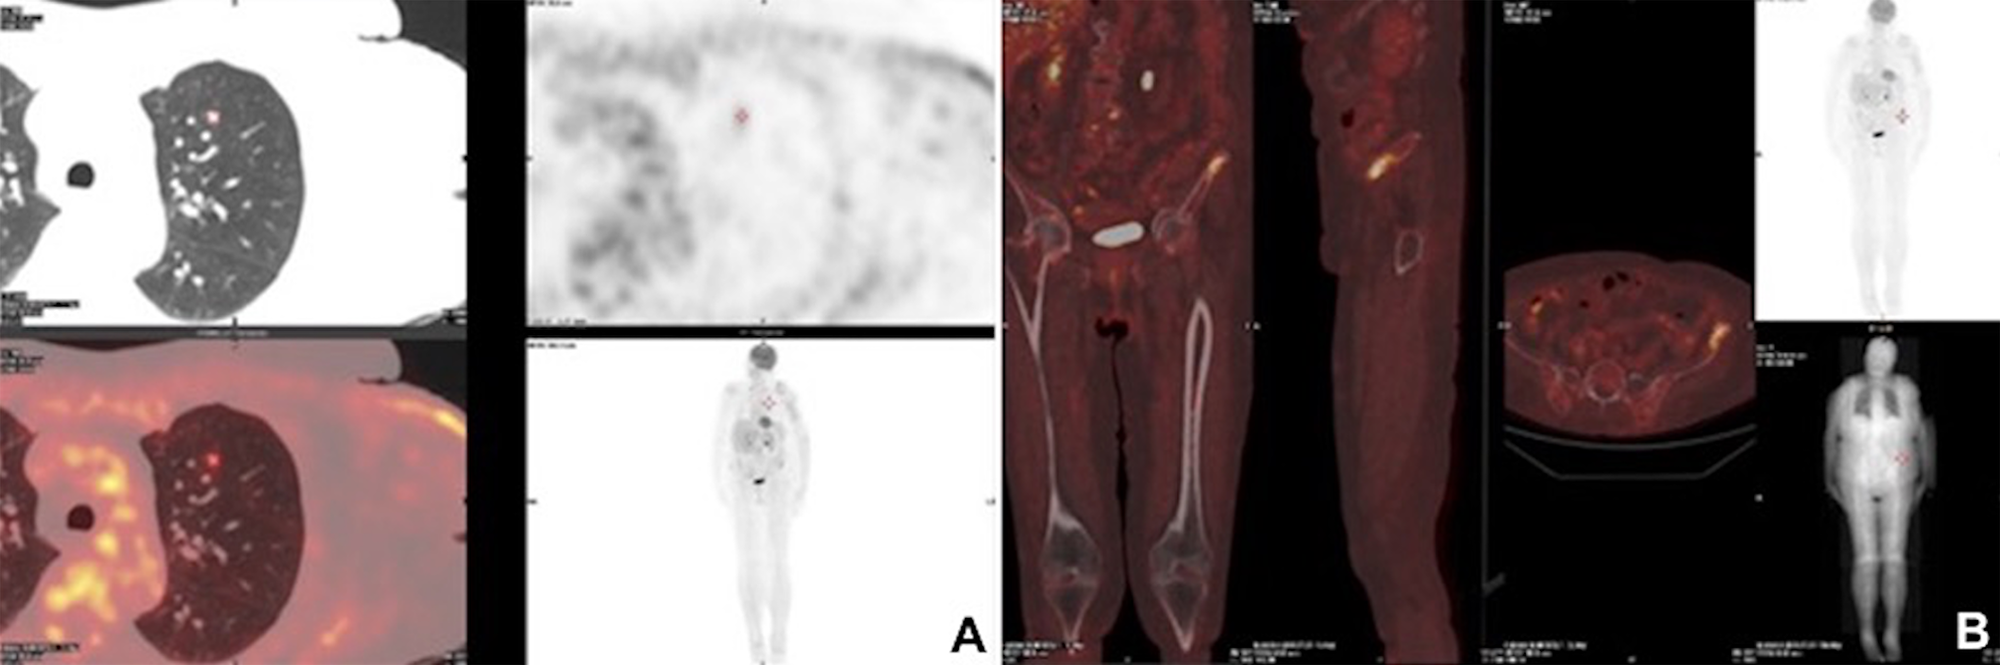

Three months post-operatively, whole-body PET/CT scan revealed a FDG-avid, presumptive pathological uptake in left lung (SUV max = 2.0) and in left iliac wing (SUV max = 7) (Figure 3). Considering the differential diagnosis, the stage and the presence of BRAF mutation, the patient appeared candidate to target therapy with BRAF-i in combination with MEK-i. This approach was shared by a multidisciplinary tumour board consultation. After fulfillment of normal echocardiography and optical coherence tomography scan, the patient started Dabrafenib 150 mg bid and Trametinib 2 mg od 4 months post-operatively. Target therapy was well tolerated. Imaging with whole-body CT scan after 4 months of combined target therapy revealed partial response in both sites of disease. In particular, there was a significant reduction in the lung metastasis (0.3 cm vs. 1 cm) and osteosclerosis of the left wing.

Postoperative radiological images

Figure 3: Postoperative radiological images. Three-months postoperative PET/CT scan showing a FDG-avid, presumptive pathological uptake in left lung (SUV max = 2.0) (A) and in left iliac wing (SUV max = 7) (B).